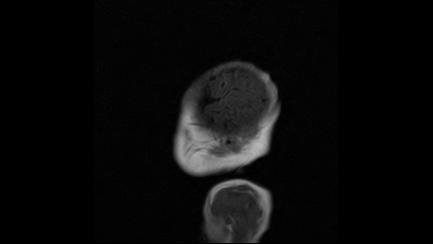

标题: PED3413:患儿女6天体检

缺血缺氧性脑病

6天为新生儿,髓鞘发育正常;左侧颞顶叶蛛网膜下腔增宽,请结合临床。

1。缺血缺氧性脑病2。左侧颞顶叶外部性脑积水,可观察

半卵圆中心上方层上可见对和乐大脑皮质t1高信号,考虑有hie可能,不知有何症状,建议加做dwi及复查

符合缺氧缺血性脑病影像表现。